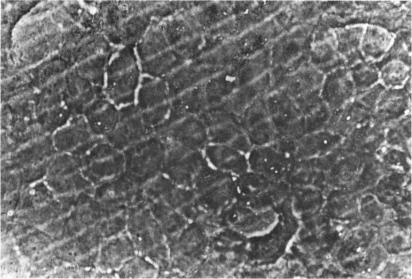

Three major pathologic processes caused by light in the primate retina: a search for mechanisms.

Trans Am Ophthalmol Soc. 1982;80:517-79.